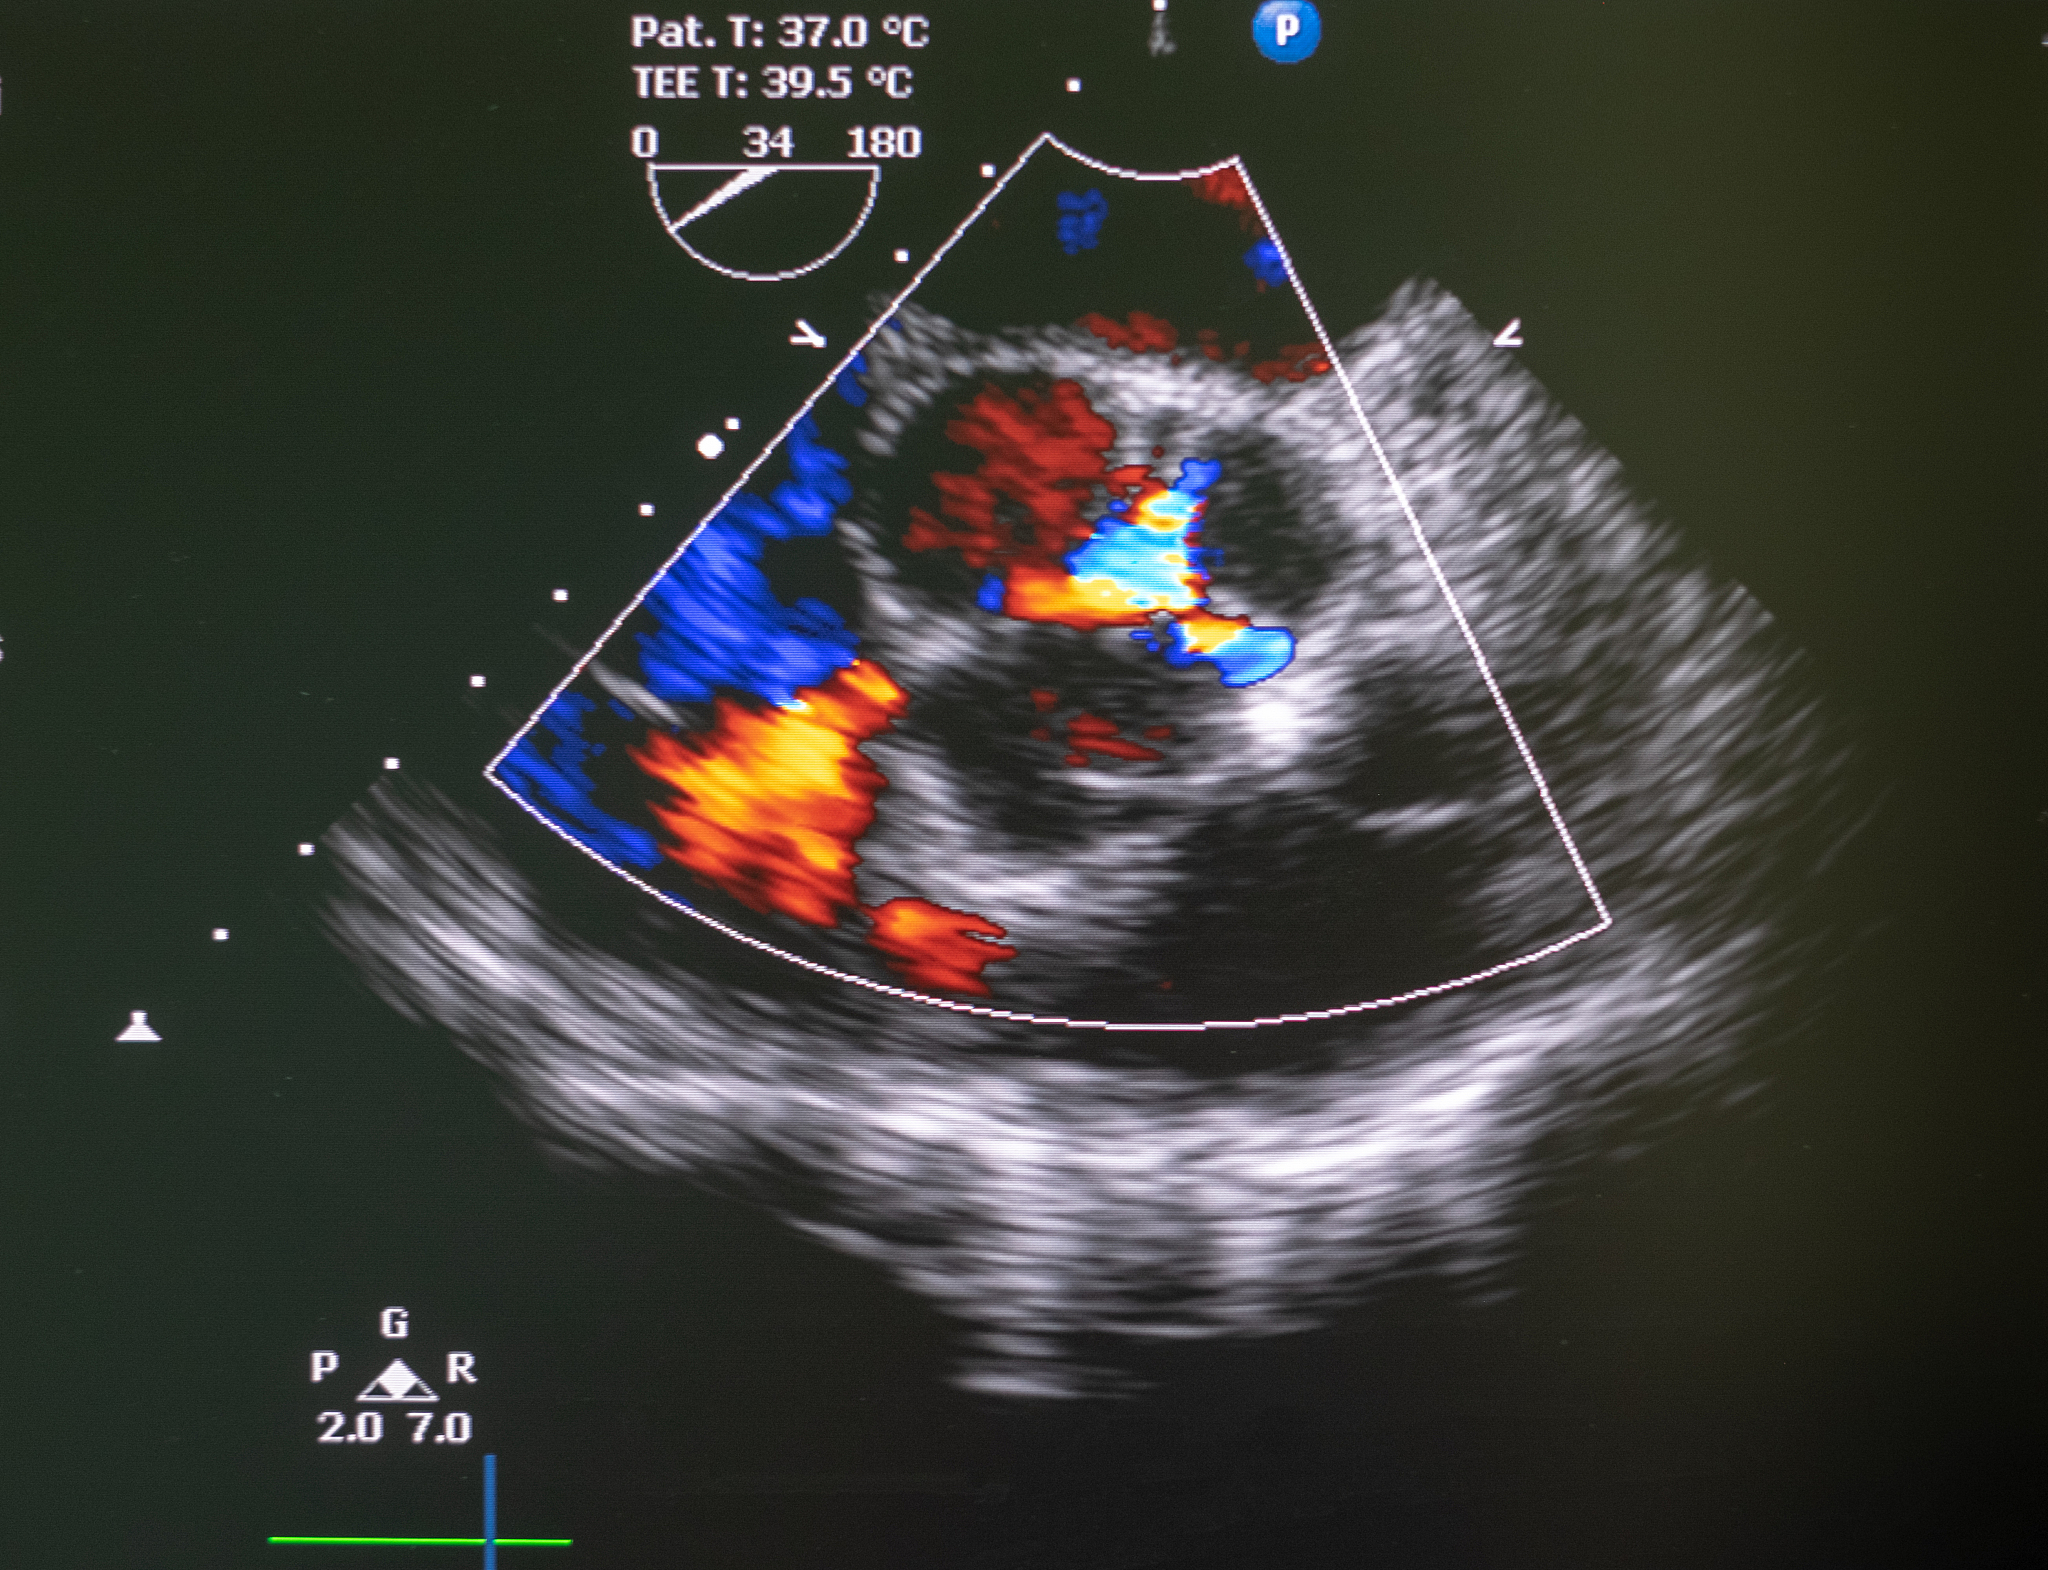

超声检查发现,该斑块的远端似可见稍低回声附着,并随颈动脉的搏动而轻微摆动。这意味着斑块远端可能与血管壁的连接不紧密,存在一定的活动性。这种情况需要密切关注,因为活动性斑块更容易脱落,形成栓子,从而增加中风的风险。